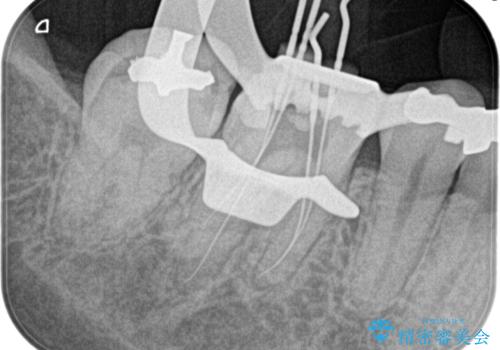

【根管治療】昨日から眠れないぐらい歯が痛い

- 昨日から夜も眠れないぐらい痛いことを主訴に来院されました。

検査の結果、不可逆性歯髄炎の診断とし根管治療を行なっております。

根管治療は1回ごとにまとまった時間で治療を行うことにより2~3回の治療で完了します。

治癒不良の場合は外科的歯内療法の適応となります。